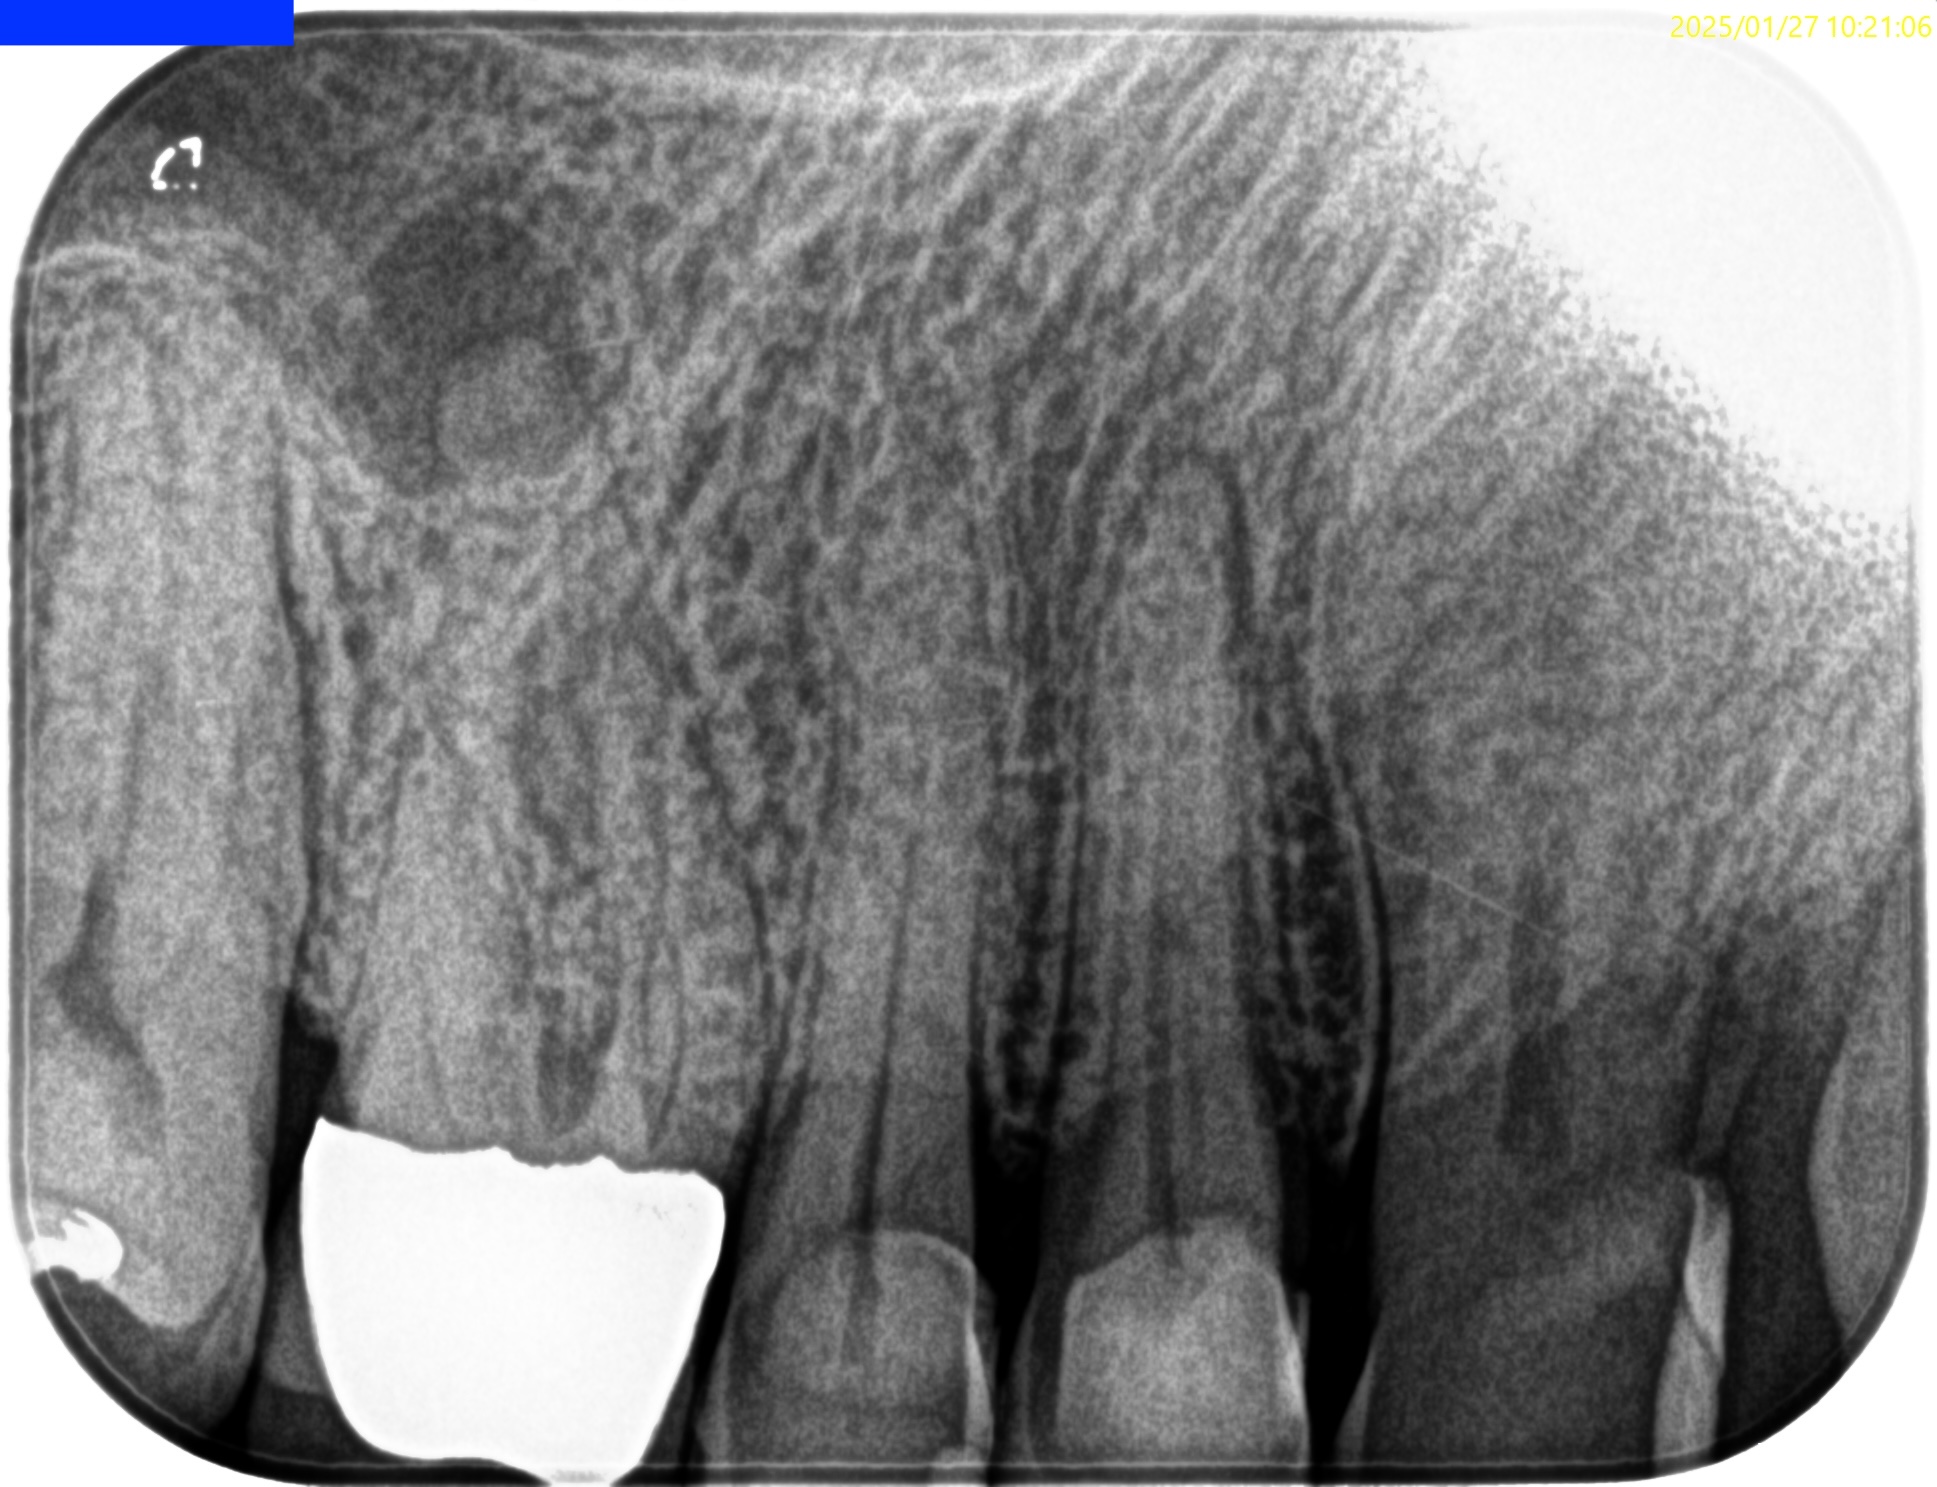

Pre-op Endo test(2025.1.27)

MB,DBのApexが歯槽骨から透けて見えている。

圧痛の原因はこれだ。

そしてSinus tract。

Pulp Dx: Pulp Necrosis

Periapical Dx: Chronic apical abscess

Recommended Tx: RCT